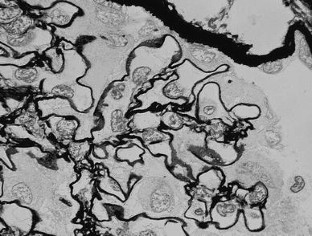

We describe a 24-year-old woman with a distinctive glomerular lesion. She presented with nephrotic syndrome and the diagnosis of systemic lupus erythematosus was made on the basis of laboratory and clinical findings. Renal biopsy showed a bubbling appearance of the glomerular capillary wall indicating lupus nephritis class V. On an electron microscopy, the glomerular basement membrane (GBM) was irregularly thickened and contained abundant vesicular and microtubular bodies. In addition, there were many epithelial foot processes infolding into the GBM. A few small deposits were observed beneath the foot processes and around the vesicular and microtubular bodies. Although the clinicopathological significance of podocytic infolding has not been fully elucidated, it may be a novel morphological entity in the glomerulonephritides.

Fig. 3